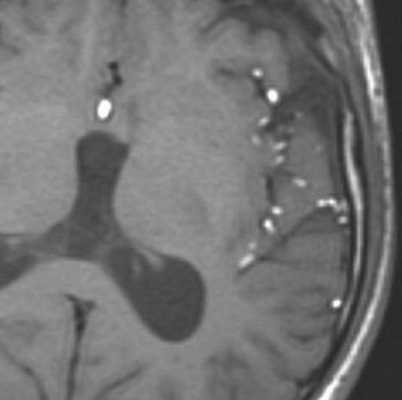

МРТ головного мозга. Т1-взвешенные корональная и сагиттальная МРТ. Эпидермоидная киста левой височной доли.

При МРТ головного мозга картина неспецифическая и зависит от содержимого кисты. Если она не содержит жира, то имеет ликворную интенсивность сигнала . В таком случае эпидермоидная киста трудно отличима от арахноидальной, хотя, как правило, не столь однородная. На МРТ типа FLAIR и диффузионно-взвешенных МРТ изображениях содержимое эпидермоидов светлее ликворного. Жировое содержимое, такие эпидермоиды еще называют холестеатомой, приводит к высокому сигналу на Т1-взвешенных МРТ головного мозга. Видимо, он обусловлен липидами, но не холестеролом. На Т2-взвешенных МРТ головного мозга он менее интенсивен чем ликвор. Контуры эпидермоидов всегда четкие. Холестеатомы составляют всего 3-5% от эпидермоидов. В 15-20% случаев встречается кальцификация по переферии кисты. Редко наблюдается контрастирование стенок.